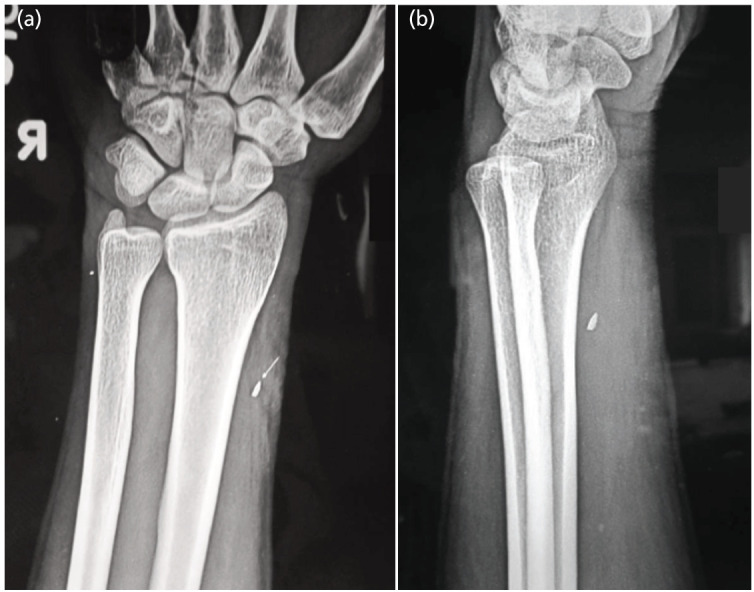

Materials and methods: This presentation is on a series of 18 cases of nerve injuries among industrial workers located from finger level up to the arm excluding the brachial plexus due to metallic foreign bodies entering while operating lathe machines over a period of two years with patients being followed-up over a one year period.

Results: Mean age in this series was 31.3 years with age range 16-40 years and all were males. Two patients had more than one nerve involvement and one patient had associated vascular injury. All the patients showed functional improvement. Most common nerve injured was median nerve. Most common site for nerve injury was forearm. Combined lesions most commonly involved the ulnar and median nerves.